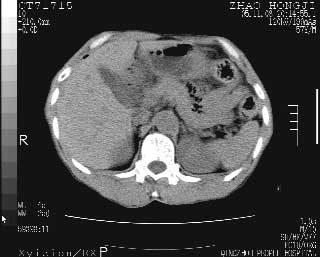

临床资料:男性,57岁,上腹部疼痛并5天,突然加重并延及全腹伴恶心5小时入院。胰淀粉酶化验在正常范围。检查:腹肌紧张,全腹压痛、反跳痛,尤以右上腹部为著。肠鸣音减低。血常规:wbc14.6x10/9, n:11.3x10/9 ,血压:135/90mmhg. 胸部透视:腹部肠腔轻度张气,未见其它异常改变。

从图提示我同意空腔脏器穿孔的诊断,来源肠道{由于病程较短,故没能见到肠系膜聚局的征象}。

肝缘见少许气体,胰尾部见少许气体包饶(蓝色圈),12指肠上部或球部邻近胆囊周边也可见少许气体影(黄色圈),并忖托出胆囊壁,12指肠远段肠道内未见明显气体(白色箭)。

消化道穿孔。12指肠球部周和胰周积气考虑12指肠穿孔可能性大。

腹腔内脂肪影密度增高,考虑腹膜炎

入院3小时后行剖腹探查术,见腹腔内大量脓性混浊液约1000ml,十二指肠球部溃疡穿孔,溃疡面约2.5x2cm,穿孔直径约0.6cm。胃内容物外益,周围组织炎性水肿明显。行十二指肠穿孔修补术。术后诊断:

1、十二指肠溃疡穿孔

2、弥漫性腹膜炎

对于少量的腹腔游离气体,ct检查较普通透视有绝对的优势,它不仅可以看到肝脏前上缘的气体,而且还能够看到小网膜区的游离气体。从而可以肯定诊断。各位分析战友的很好,感谢大家的参入!